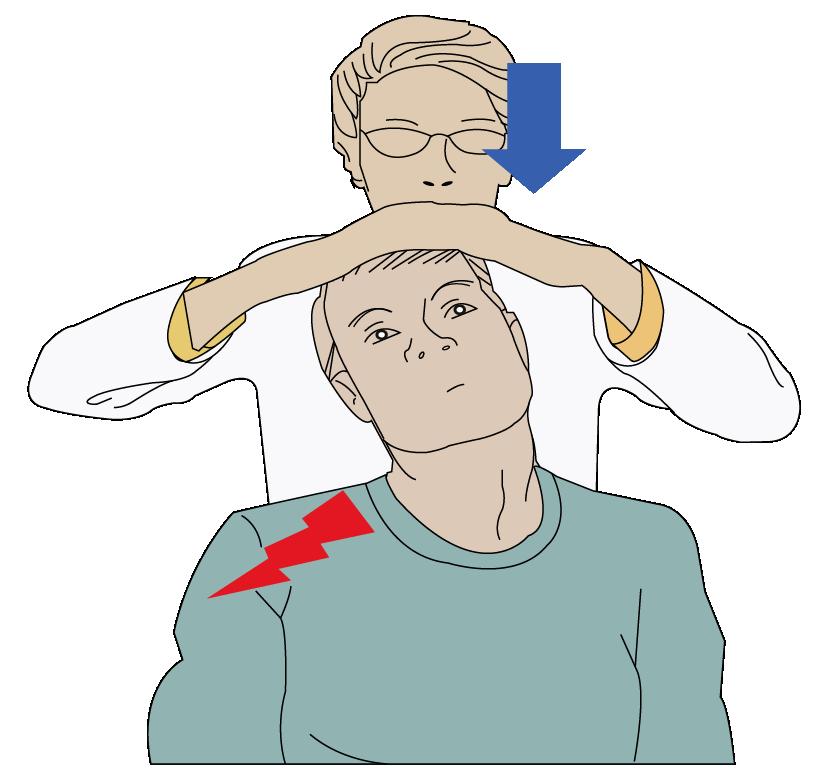

Diagnóstico

El paciente cursa con dolor en el miembro superior del mismo lado de la herniación (cervicobraquialgia), se puede realizar las maniobras de Spurling y de alivio del dolor (abducción).

Si llega a tener afectación motora será la imposibilidad de extender el codo, flexionar y extender la muñeca y perdida del reflejo tricipital.

El examen por solicitar es la RMN donde se evidenciaría la herniación foraminal con mayor frecuencia.